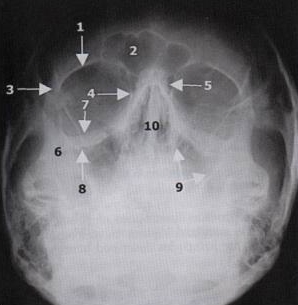

Waters View

• Most Valuable

• Screening Tool

• Evaluation Midface

• Dolan Evaluation Method

• Four  Curvilinear To Observing For Asymmetry